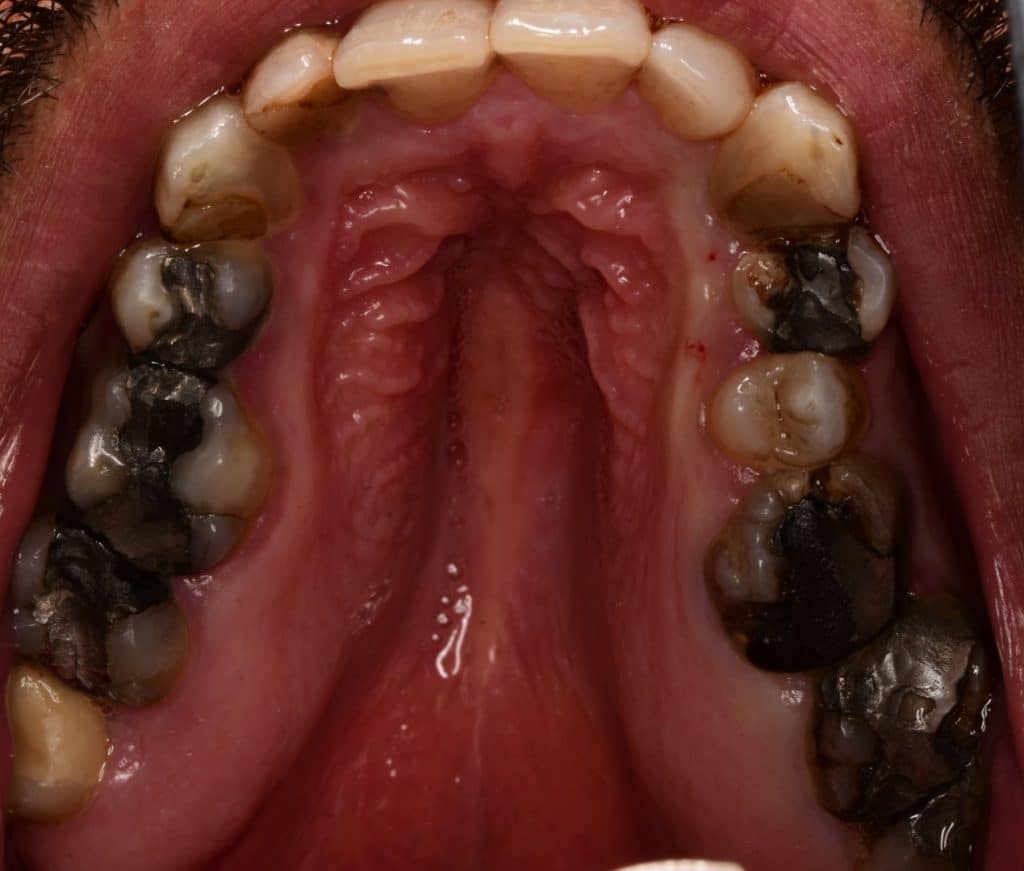

Initial situation as you can see the black upper jaw because of amalgam fillings